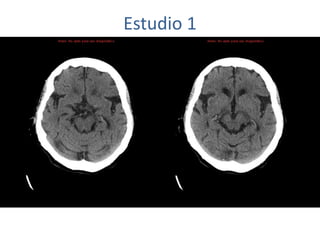

Estudio 1